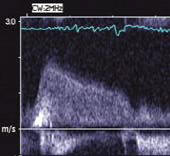

CW Doppler: diastolic flow through the foramen connencting the accessory chamber to the left atrium